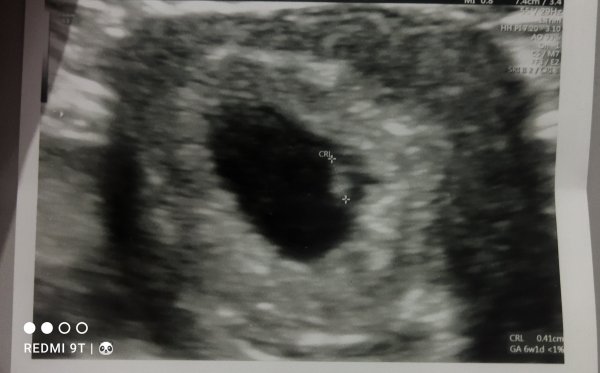

• IMG_20230217_204429.jpg

IMG_20230217_204429.jpg

33,2 KB · Görüntüleme: 163

Selamlar, malesef üzerinde tahmin yapılamayacak kadar kötü, ilerleyen zamanlarda yenisi gelir ise atarsınız. Sevgiler. ( bulanık anlaşılmıyor )

Aslında gerçekten insan çok heyecanlaniyor ilk gebeliğim arkadasim geçen hafta bır guruba yazmış bende merak ettim tabi yinede en iyisini Allah bilir fakat yine insanı tatlı bir merak sarıyor teşekkür ederim şimdiden canım.